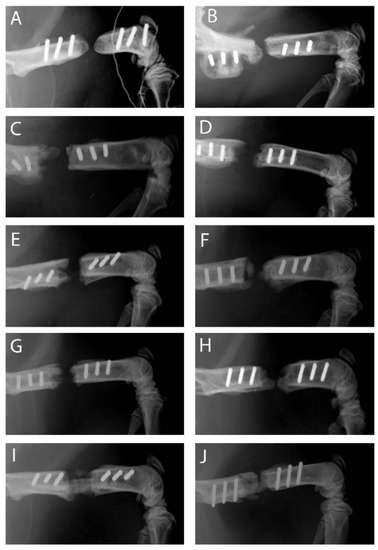

2.2. Course of Bone Regeneration